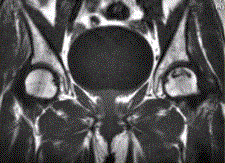

问题 患者男,47岁,左髋部疼痛及压痛6个月,“4”字试验阳性。左髋关节内、外旋活动受限。检查提示:左髋关节活动轻度受限,大腿上部轻压痛。血常规检查正常。髋关节CT及MRI如下图。 根据髋关节CT和MR影像,你认为此病例的影像学表现有

选项 A.CT检查未见异常 B.左侧股骨头内可见线样高密度影 C.左股骨头塌陷变扁,其内可见条带状硬化 D.左股骨头内见蜿蜒走行的T1、T2低信号条带影 E.左髋关节腔内可见弧线状长T1、长T2信号 F.左髋关节间隙变窄

答案 BDE